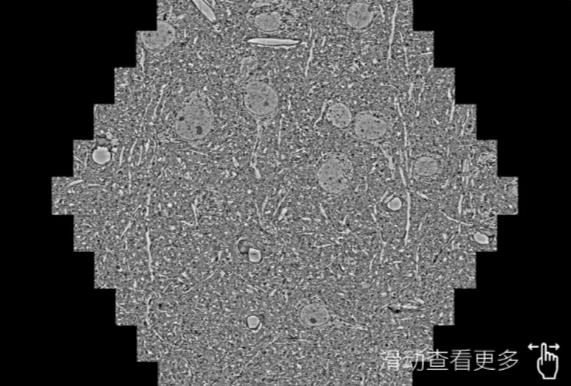

鼠脑切片。左图使用宁夏蔡司宁夏扫描电镜MultiSEM706对165μmx143pm面积区域成像,耗时仅需1.5秒。右图为鼠脑切片中30μm区域放大效果。样品由芝加哥大学B.Kasthuri提供。

使用蔡司高速宁夏扫描电镜MultiSEM对1mm²人脑皮层组织进行高分辨成像,并对其中的各种细胞结构进行三维重构分析。左图展示了2x3mm²组织平面中锥体神经元的三维重构效果。右图显示了局部体积神经元三维重构。图像由哈佛大学chtman实验室提供,渲染图由D. Berger 制作。